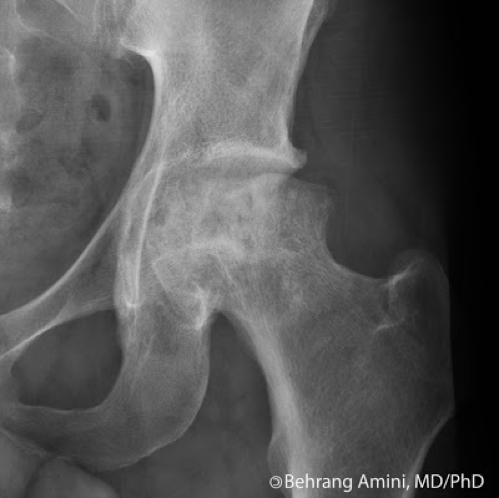

what is there an increased prevalence of in the femoral head

avascular nerosis - may relate to steroids use